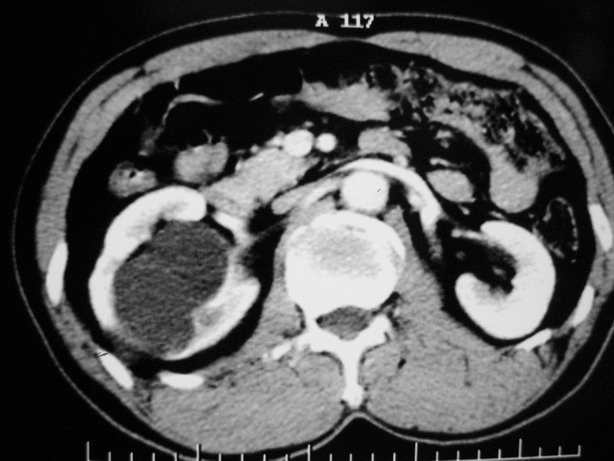

标题: CT10772:男性,48,右肾盂旁多囊性占位! [打印本页]

标题: CT10772:男性,48,右肾盂旁多囊性占位!

男性,48,体检发现,平时无症状。

增强:

肾盂旁多囊性占位,有实性成分,增强有轻度强化,收集期病变内无造影剂显影。诊断肾盂旁囊肿,有实性成分无法解释,查书后诊断为:多房性囊性肾瘤!!不知大家同意否?????????对本病知道不多,望大家不吝赐教!!